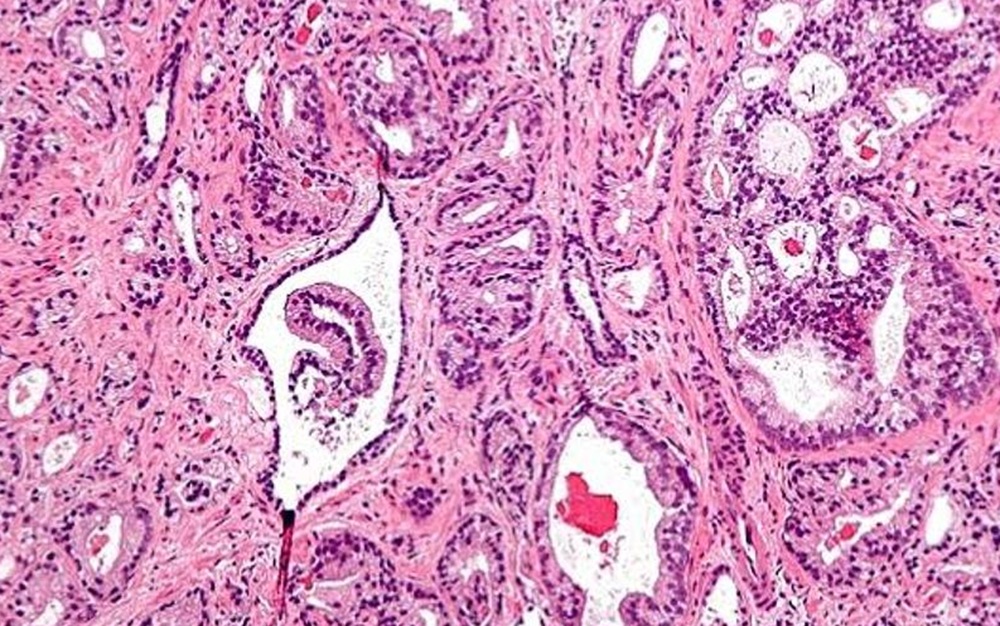

Histología de células tumorales en cáncer de próstata. Histología de células tumorales en cáncer de próstata.